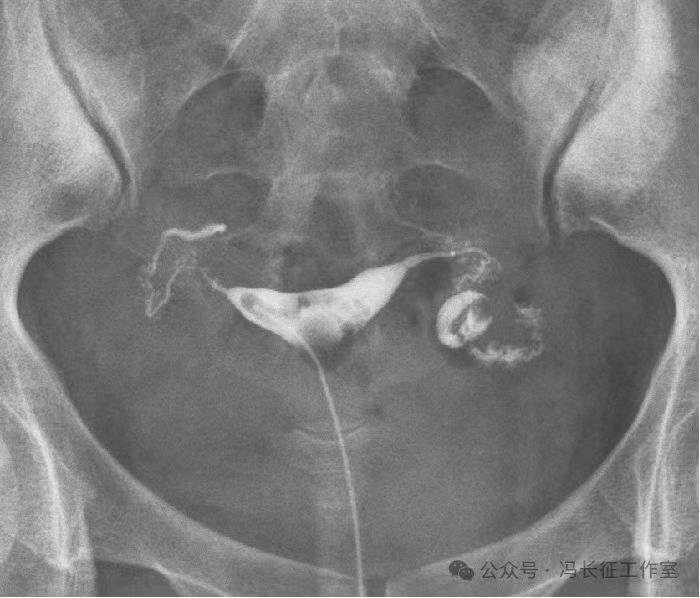

输卵管积水的子宫输卵管造影尽量包括这5个方面的描述,诊断的临床意义才最大,这样才能给好的生殖科医生有价值的建议,帮助给不孕者制定最好的助孕治疗方案。比如这例输卵管积水,峡部结节性输卵管炎(病因),交通性(积水近端是否和宫腔相通),中度(积水大小),厚壁(管壁的厚度),多囊(囊腔的多少)。

微信图片_20240220111200(4).jpg

最后诊断应该是:双侧峡部结节性输卵管炎并双侧中度、厚壁、多囊、交通性输卵管积水。